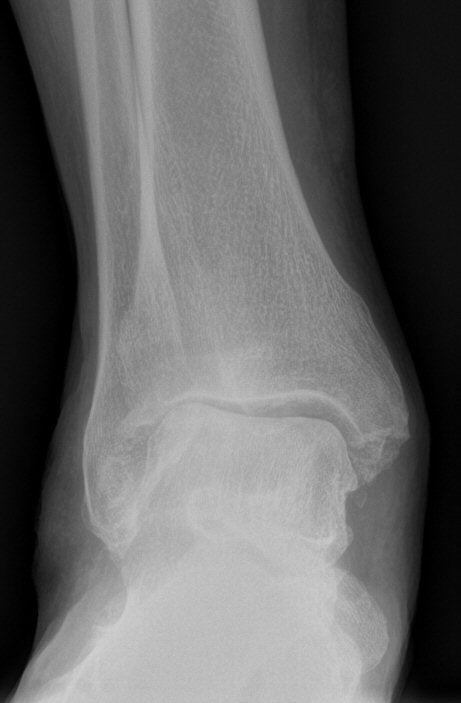

Diagnos

- Symtom enligt ovan i kombination med typiska röntgenfynd enligt nedan.

Klassificering

Takakura: [2]

- Stadie I: Osteofyter men bevarad ledspringa

- Stadie II: Minskad ledspringa men ej benkontakt

- Stadie IIIA: Benkontakt vid mediala malleolen

- Stadie IIIB: Benkontakt talus-troklea mot tibia

- Stadie IV: Komplett benkontakt

- Belastad slätröntgen, inför beslut om protes eller tibiaosteotomi så belastad slätröntgen med "long axial view".